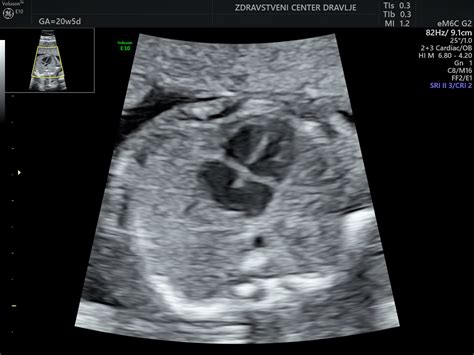

- Oblikovanje organov: Možgani, hrbtenjača, srce, ledvice in želodec dobivajo svojo pravo obliko. Srce je že razdeljeno na štiri votline, vključno z aortno in pljučno zaklopko, ter ima že levi in desni prekat. Bije mu z dvakratno hitrostjo vašega srca, torej približno s 150 udarci na minuto, kar zagotavlja učinkovito oskrbo z vsemi potrebnimi snovmi za nadaljnji razvoj.